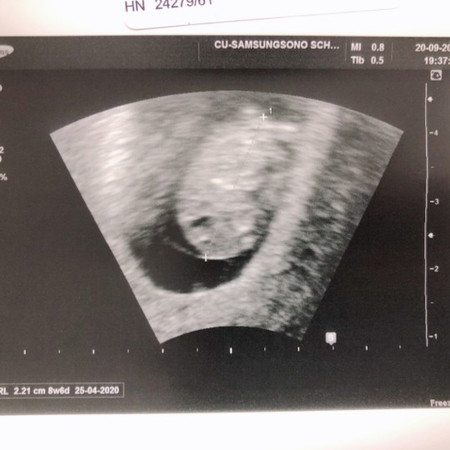

สอบถามแม่ๆท่านไหนที่ทำอัลตร้าซาวด์ดูหัวใจลูก แล้วพบ ว่ามีก้อนเนื้ออยู่หลังโพรงมดลูก และหมอยังไม่แน่ใจว่าเป็นอะไร ซึ่งมดลูกและรังไข่ก็ปกติดี และท้องในโพรงมดลูกตัวเล็กมีหัวใจแล้ว ทุกอย่างปกติ แต่กังวลเจ้าก้อนเนื้อเนี่ยค่ะ แม่ๆท่านไหนซาวด์แล้วพบปัญหาเหมือนแม่บ้านนี้ย้างค่ะแชร์ประสบการณ์หน่อยค่ะ....ขอบคุณค่ะ